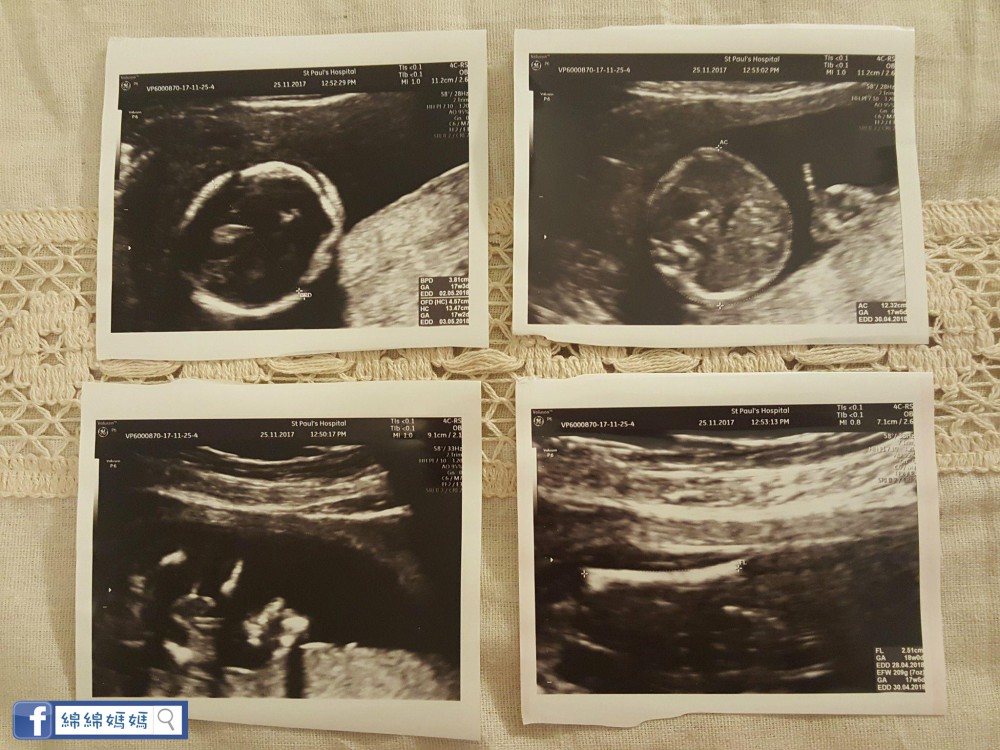

呢日係18W+3D, St.Paul 做檢查,過左12W, 私家醫生暫時見議我一個月產檢一次。

呢日係21W,終於等到呢一日喇,點解咁期待? 因為返瑪嘉烈醫院幫 "綿綿" 照結構。之前都有聽好多朋友或網上媽媽講,政府照得比較馬虎, 所以我都有book定一個私家醫生作後備,

最後聽到醫生話BB一切正常,係仔仔, 好健康,我同老公即時安心晒~

另外Book左私家醫生照結構,我都打去Canel 左,因為我對BB有信心,唔想再照喇~